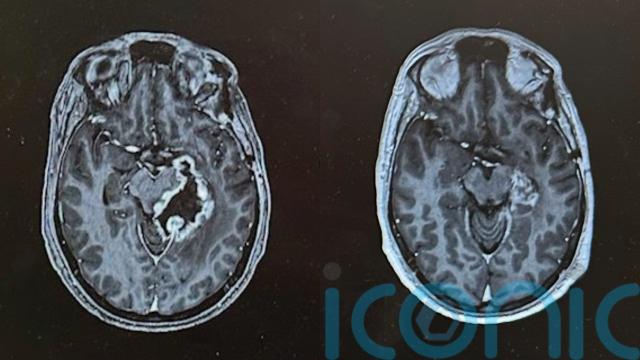

“Things stabilised for a little bit, but the MRI scans I was having still showed the tumour was fairly large,” he said.

After just six sessions, an MRI scan revealed that the tumour had reduced in size from seven to 1.7 centimetres in diameter.